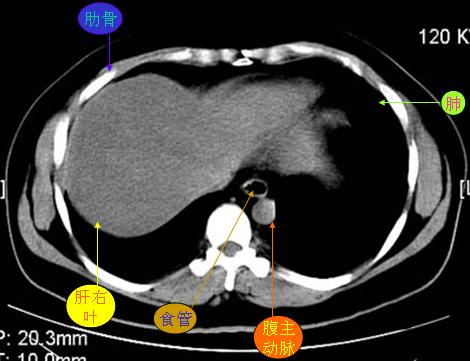

腹部ct解剖与基本病变